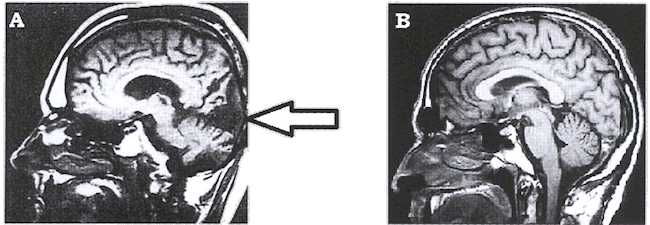

Document A : IRMf d'un patient aveugle suite à un accident

vasculaire

Document B : IRMf d'un sujet sain

Le tissu cérébral sain apparaît en niveaux de

gris plus ou moins clair. Une zone habituellement claire, devenue

noire, peut être interprétée comme une zone

lésée inactive.

Le document 2 localise (flèche) une unique zone

sombre lésée